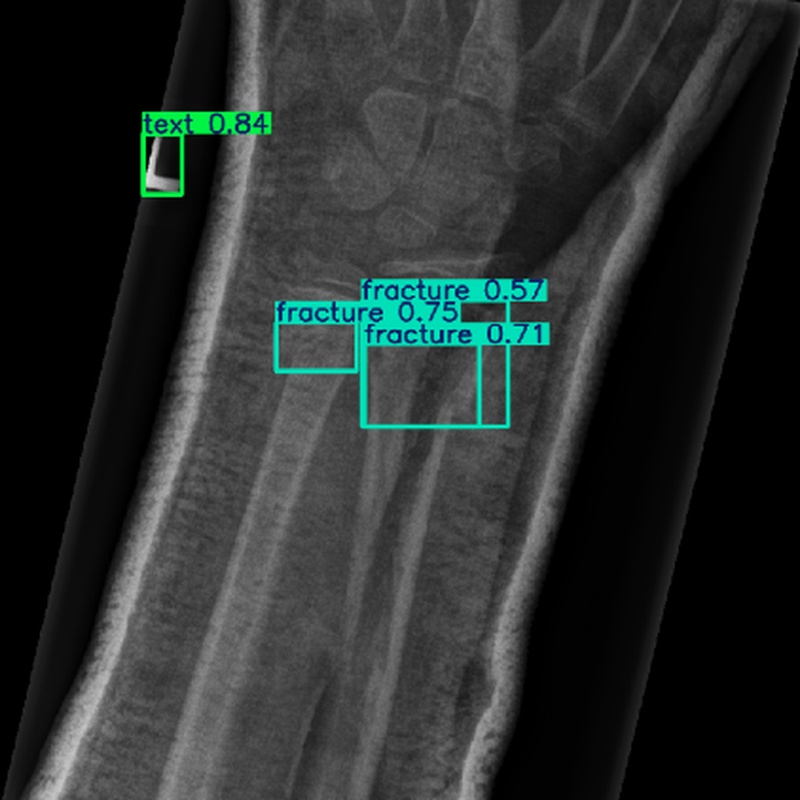

现场环境 在医学成像环境中,使用X射线、CT或MRI等设备获取图像。图像采集过程中可能存在噪声干扰,且骨折目标通常较小,仅占图像像素的2.3%左右,需要在低对比度和复杂背景的条件下进行检测。

使用对象 医学图像中的骨折区域,包括不同类型的骨折(如骨异常、骨损伤等),尤其是小目标骨折区域。

输出数据 骨折检测结果,包括骨折区域的边界框坐标、类别标签(如骨折、金属等)以及置信度。

测试结果 在测试集上,ASC-YOLO模型实现了61.1%的mAP@50,比基线YOLO模型提高了7.4%。断裂类别的mAP@50达到95%,金属类别的mAP@50达到97%。